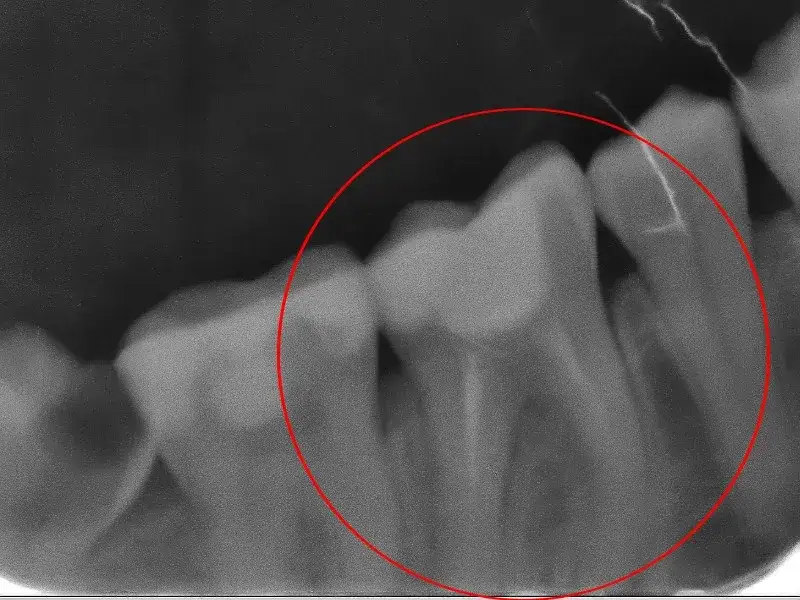

Przepchnięcie materiału wypełniającego: jakie są konsekwencje?

Przepchnięcie materiału wypełniającego poza kanały korzeniowe to poważne ryzyko związane z leczeniem endodontycznym. Taka sytuacja może prowadzić do stanów zapalnych, a nawet infekcji, co znacząco wpływa na proces regeneracji zęba po leczeniu. Pacjenci często skarżą się na nasilenie bólu, co wymaga dodatkowej interwencji.

Możliwe komplikacje obejmują rozwój ropnia oraz przewlekłego bólu. Dlatego tak ważne jest, aby stomatolog był odpowiednio wykwalifikowany i stosował najlepsze praktyki podczas zabiegu.